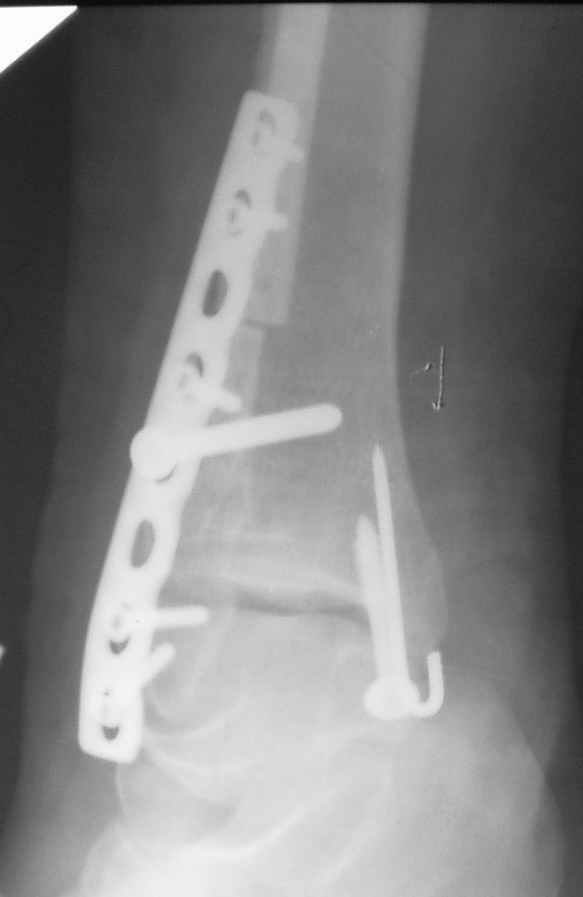

Уважаемые коллеги! Персонально, дорогой доктор Джолдас. Не знаю, почему почта к тебе не проходит - у меня почтовая программа "Bat", снимки в JPG. Выставляю через форум. 10 апреля я показывал снимки больной с застарелым переломо-вывихом голеностопного сустава. 9 июня прооперировал, снимки прилагаю. R-контроль через месяц ходьбы на костылях, все стоит также. Разрешил частичную (20кг) нагрузку на ногу, пока жалоб нет. Ход операции - сагиттальная остеотомия по линии неправильно сросшегося перелома малоберцовой кости, остеотомия с формированием внутренней лодыжки, попытка вправления подвывиха неудачна из-за того, что "не хватало" длины малоберцовой. Остеотомия малоберцовой кости выше синдесмоза. Остеосинтез.

На снимках хорошо сохранный голеностопный сустав, подвывих устранен, суставная щель одинаково прослеживается со всех сторон, небольшая нехватка длины малоберцовой и немного выступает пластина, а так в целом репозиция и фиксация удалось. Иногда, синдесмотический шуруп мы вводим немного длиннее, примерно на 3мм за медиальный кортекс, при переломе шурупа после нагрузки, шуруп легко удаляется с медиальной стороны. После 6 недель в гипсе можно разрешить нагрузку.